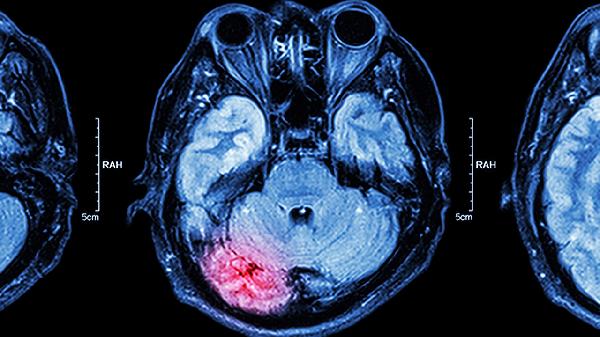

脑供血不足患者除药物治疗外,应保持低盐低脂饮食,适量进行有氧运动如散步、太极拳等。避免长时间低头或保持固定姿势,定期监测血压、血糖等指标。若症状持续加重或出现肢体麻木、言语不清等表现,须及时就医进行头颅CT或MRI检查。